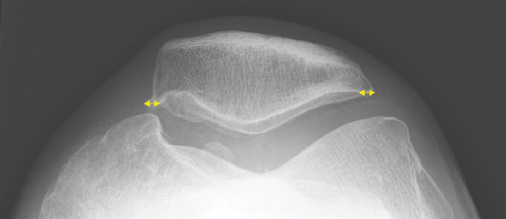

Konsensusempfehlung BK 2112 Gelenkspalt-verschmälerung

Basierend auf Normwerte nach Lanyon (1998), der Gelenkspaltmessungen an 86 Frauen und 39 Männern ohne Kniebeschwerden und ohne Osteophyten durchgeführt hatte (Altersverteilung 40–75 Jahre, Durchschnittsalter 58 Jahre), einigte sich die Konsensusgruppe auf folgende Werte für eine vorliegende Gelenkspaltverschmälerung: siehe   Tabelle 2 für das Femorotibialgelenk und   Tabelle 3 für das Patellofemoralgelenk.

Falls eine grenzwertige Gelenkspaltverschmälerung vorliegen sollte, wird empfohlen, bereits vorhandene Magnetresonanztomographie- (MRT-) und/oder Arthroskopiebefunde als aussagekräftigere Methoden im Vergleich zu der Projektionsradiographie zu werten und in die Entscheidung bezüglich des Vorliegens einer Arthrose einzubinden. Sollte eine Klärung durch bereits vorhandene Unter-suchungen nicht möglich sein, sollte ggf. zur Verifizierung eines mög-lichen Knorpelschadens ein ergänzendes MRT angefertigt werden.